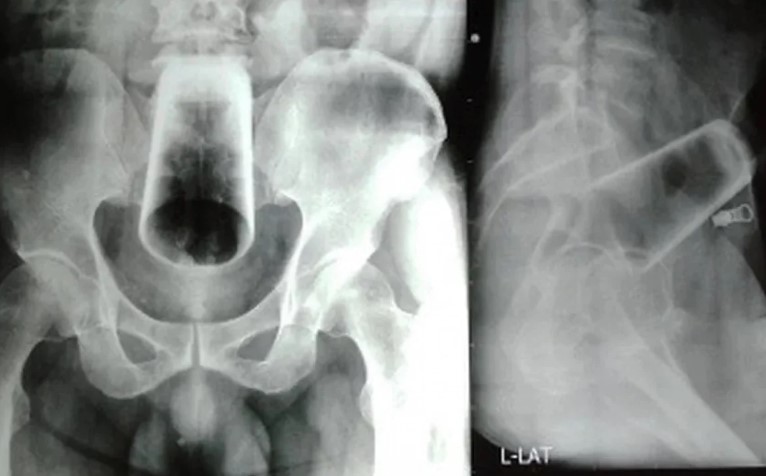

Exame de radiografia mostra copo de vidro no intestino de um homem nepalês

Exame de radiografia mostra copo de vidro no intestino de um homem nepalês (Foto: Reprodução)

As imagens da radiografia viralizaram nas redes sociais. nelas, é possível ver que o copo estava em posição invertida.